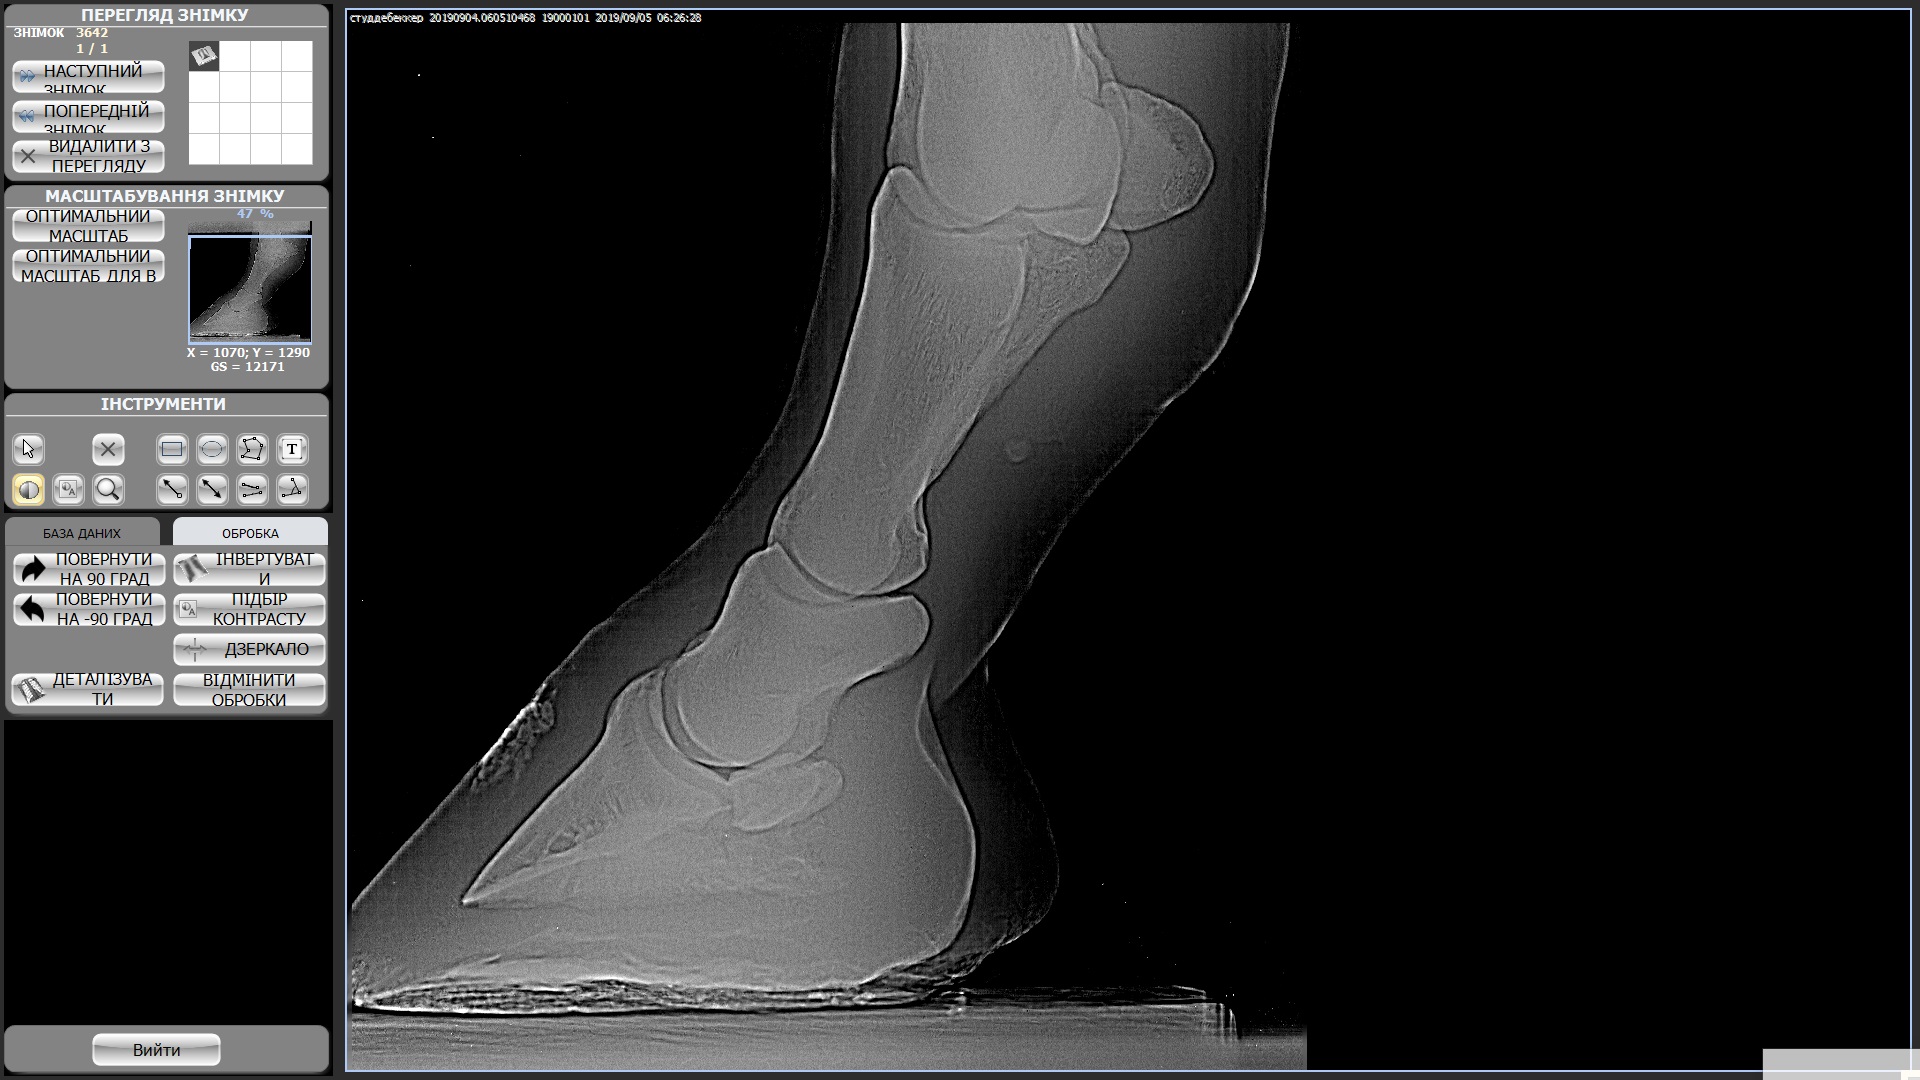

Мерин 7 лет, купили в этом году, смотрели с ветом и делали рентгены ног, прикрепила к теме. Были микротравмы суставов из за чего появляются наливы (мягкие шишки) на суставах всех 4х ног. Приглашала другого вета сказал менять постав подковами ортопедическими, так и сделали после чего конь захромал на правый перед и оба зада, проходили так неделю и сняли подковы - хромота ушла, но копытные остались налитыми, как и шишки не сошли. Вроде бы все было хорошо на протяжении 2х недель, наливы не сошли, но конь на них не жалуется. И вот на днях ходили в поля (только шагом), пару раз нас напугала то машина, то веточка и он подрывался немного. На следующее утро хромает на все 4, щупали мышцы и смотрели наливы изменений нет но конь хромает на все 4 и немного теплые копытные((((

Студдебекер 3 ЗЛ.jpg494 KB · Просмотры: 366 -

студебеккер 2 ЗП.jpg404.4 KB · Просмотры: 370 -

СтудебеккерПЛ.jpg489.8 KB · Просмотры: 327 -

Студебеккер ПП.jpg528.2 KB · Просмотры: 411 -